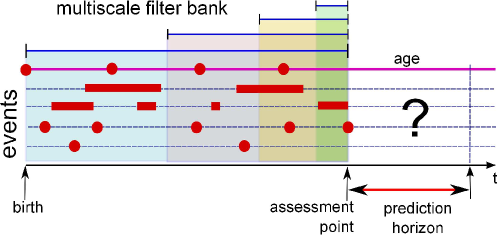

The framework is built on the patient-specific data queried from the relational EMR systems (denoted as A in Fig. 1). Patient data contains time-stamped events (such as emergency visits, diagnoses, and hospitalizations) and static information (such as gender, spoken language and occupation). For each patient, there are one or several evaluation points from which future risk will be predicted (Fig. 2). Often clinical risk assessments, hospital admissions or discharges serve as natural evaluation points as the outcomes will be tracked and acted upon.

In general, medical records for each patient contain time-stamped events of different types. Thus the EMR at a given time can be represented as a sparse 2D image (see Fig. 2). One dimension is time and the other dimension represents events. The events are sparse and irregular because clinical events are often packed into episodes. A typical episode starts with an emergency visit followed hospitalization and ends with discharge or death. For certain conditions such as mental health and cancers, formal risk assessments may be performed. Emergency visits, hospitalizations and risk assessments are major events that contain sub-events. For example, each emergency visit includes a primary ICD-10 diagnosis code, a decision to admit, transfer or return home. Hospitalization could be planned or come through the emergency department. Each admission typically contains multiple diagnoses, intervention procedures and medication prescriptions. A risk assessment may contain a check list or ordinal ratings on multiple risk-related items.

4.2 Multiscale Feature Extraction using One-Sided Filter Bank

Our prediction problem is to stratify future risk within a window of time using historical records. Thus at a prediction point, we transform the EMR into a feature vector to which risk classifiers are applied. As medical events are irregular and sparse, standard feature extraction techniques that rely on precise timing may not be robust. Instead, we exploit the 2D temporal image representation using a bank of one-sided filters. The concept resembles filters in signal processing and vision, except that the “signals” are sparse and irregular, also no future information will be used as the filter is one-sided.

Let be the time point of interest, be the maximum history length. Let be the observation of the event of type at time , for . Discrete events such as diagnosis are typically binary, i.e., are the presence or absence of a code. For continuing events such as treatment episodes, is the event duration. Let be a kernel function of , parameterized by and right-truncated at – that is, for . The -th feature evaluated at for event is defined using the following convolution operation:

where denotes the delay. When , the kernel is effective at anytime before time . In effect, the event sequence of type is summarized throughout the history of length by the convolution operation. However, when , the kernel is ineffective until . This is equivalent to evaluating the feature at , and thus this captures the temporal progression from to .

The adjustable kernel parameter controls the effective range of the kernel. This is important to differentiate acute conditions (such as suicide ideation) from chronic conditions (such as Type I diabetes). One useful kernel is the truncated Gaussian